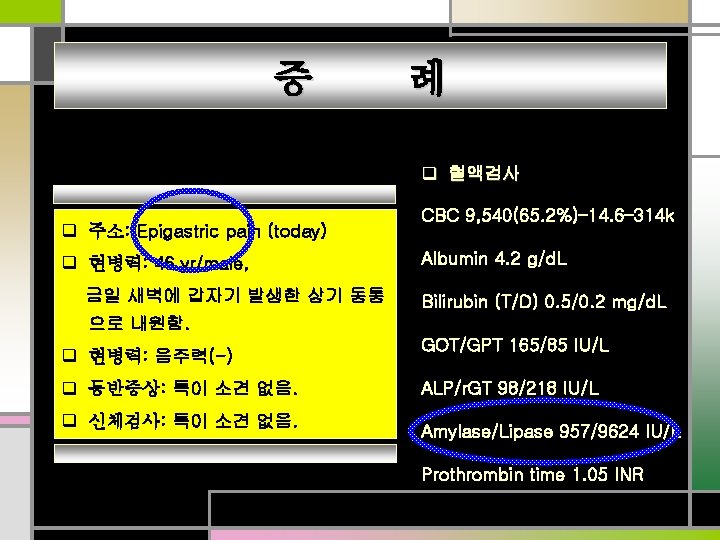

증 례 q 혈액검사 q 주소: Epigastric pain (today) q 현병력: 46 yr/male, 금일 새벽에 갑자기 발생한 상기 동통 CBC 9, 540(65. 2%)– 14. 6– 314 k Albumin 4. 2 g/d. L Bilirubin (T/D) 0. 5/0. 2 mg/d. L 으로 내원함. q 현병력: 음주력(-) q 동반증상: 특이 소견 없음. q 신체검사: 특이 소견 없음. GOT/GPT 165/85 IU/L ALP/r. GT 98/218 IU/L Amylase/Lipase 957/9624 IU/L Prothrombin time 1. 05 INR